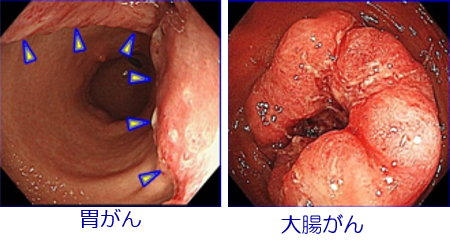

≪消化管のがん≫

大腸がん、胃がんを中心に当科では最新の治療ガイドラインをベースとした治療を行っています。進行がんであっても新規薬剤(分子標的治療薬や免疫チェックポイント阻害剤など)を含めた薬物治療や手術を中心とした集学的治療により長期生存が得られる症例も増えてきております。また、閉塞性大腸癌に対して消化管ステントを挿入し、精査ののちに腹腔鏡下で切除術を行うことで以前のように人工肛門を造設することも少なくなってきました。このように進行がんでも治療成績は良くなってきておりますが、より良い治療結果のためには早期発見が大切ですので、積極的に検査を受けていただくように当科ではお勧めしております。